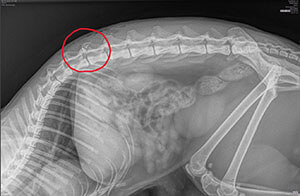

Frau Schuler hat ihren Kater Tyga mit gelähmten Hinterbeinen und einer Wunde am Rücken aufgefunden und ist sofort in eine Tierklinik. Dort wurde ihr mitgeteilt, dass das Röntgenbild nicht schlüssig sein und zuerst noch ein CT gemacht und anschliessend operiert werden müsse. Tyga sei vermutlich angeschossen worden. Sie verlangten eine Vorauszahlung von CHF 2'000.- in bar. Tyga lag in der der Klinik ohne dass sein Schlafplatz gereinigt worden wäre. Schlussendlich haben die Tierärzte empfohlen Tgy einzuschläfern. Entsetzt hat uns Frau Schuler voller Verzweiflung angerufen und gefragt, ob wir ihr helfen können. Wir haben Frau Schuler in die Tierklinik Aarau West geschickt, wo sie freundlich empfangen wurde.

Tyga wurde eingehend – auch neurologisch - untersucht und die Wunde am Rücken versorgt. Er wurde vorerst nicht operiert, da die Ärzte befürchteten, dass ein Eingriff die Wunde verschlimmern und das Risiko einer Infektion erhöhen könnte. Stattdessen wurde er medikamentös behandelt und erhielt zusätzlich physiotherapeutische Unterstützung. Ein CT oder MRI dränge sich im Moment nicht auf. Mittlerweile durfte er wieder nach Hause kommen. Bei der Nachkontrolle wurde entschieden, dasss auf eine Operation verzichtet werden kann. Ich bin sehr zuversichtlich, da Tyga bereits bemerkenswerte Fortschritte gemacht hat - er kann schon wieder laufen und steht sicher auf allen vier Beinen. Springen, hüpfen und sich kratzen ist noch nicht wirklich der Fall.»